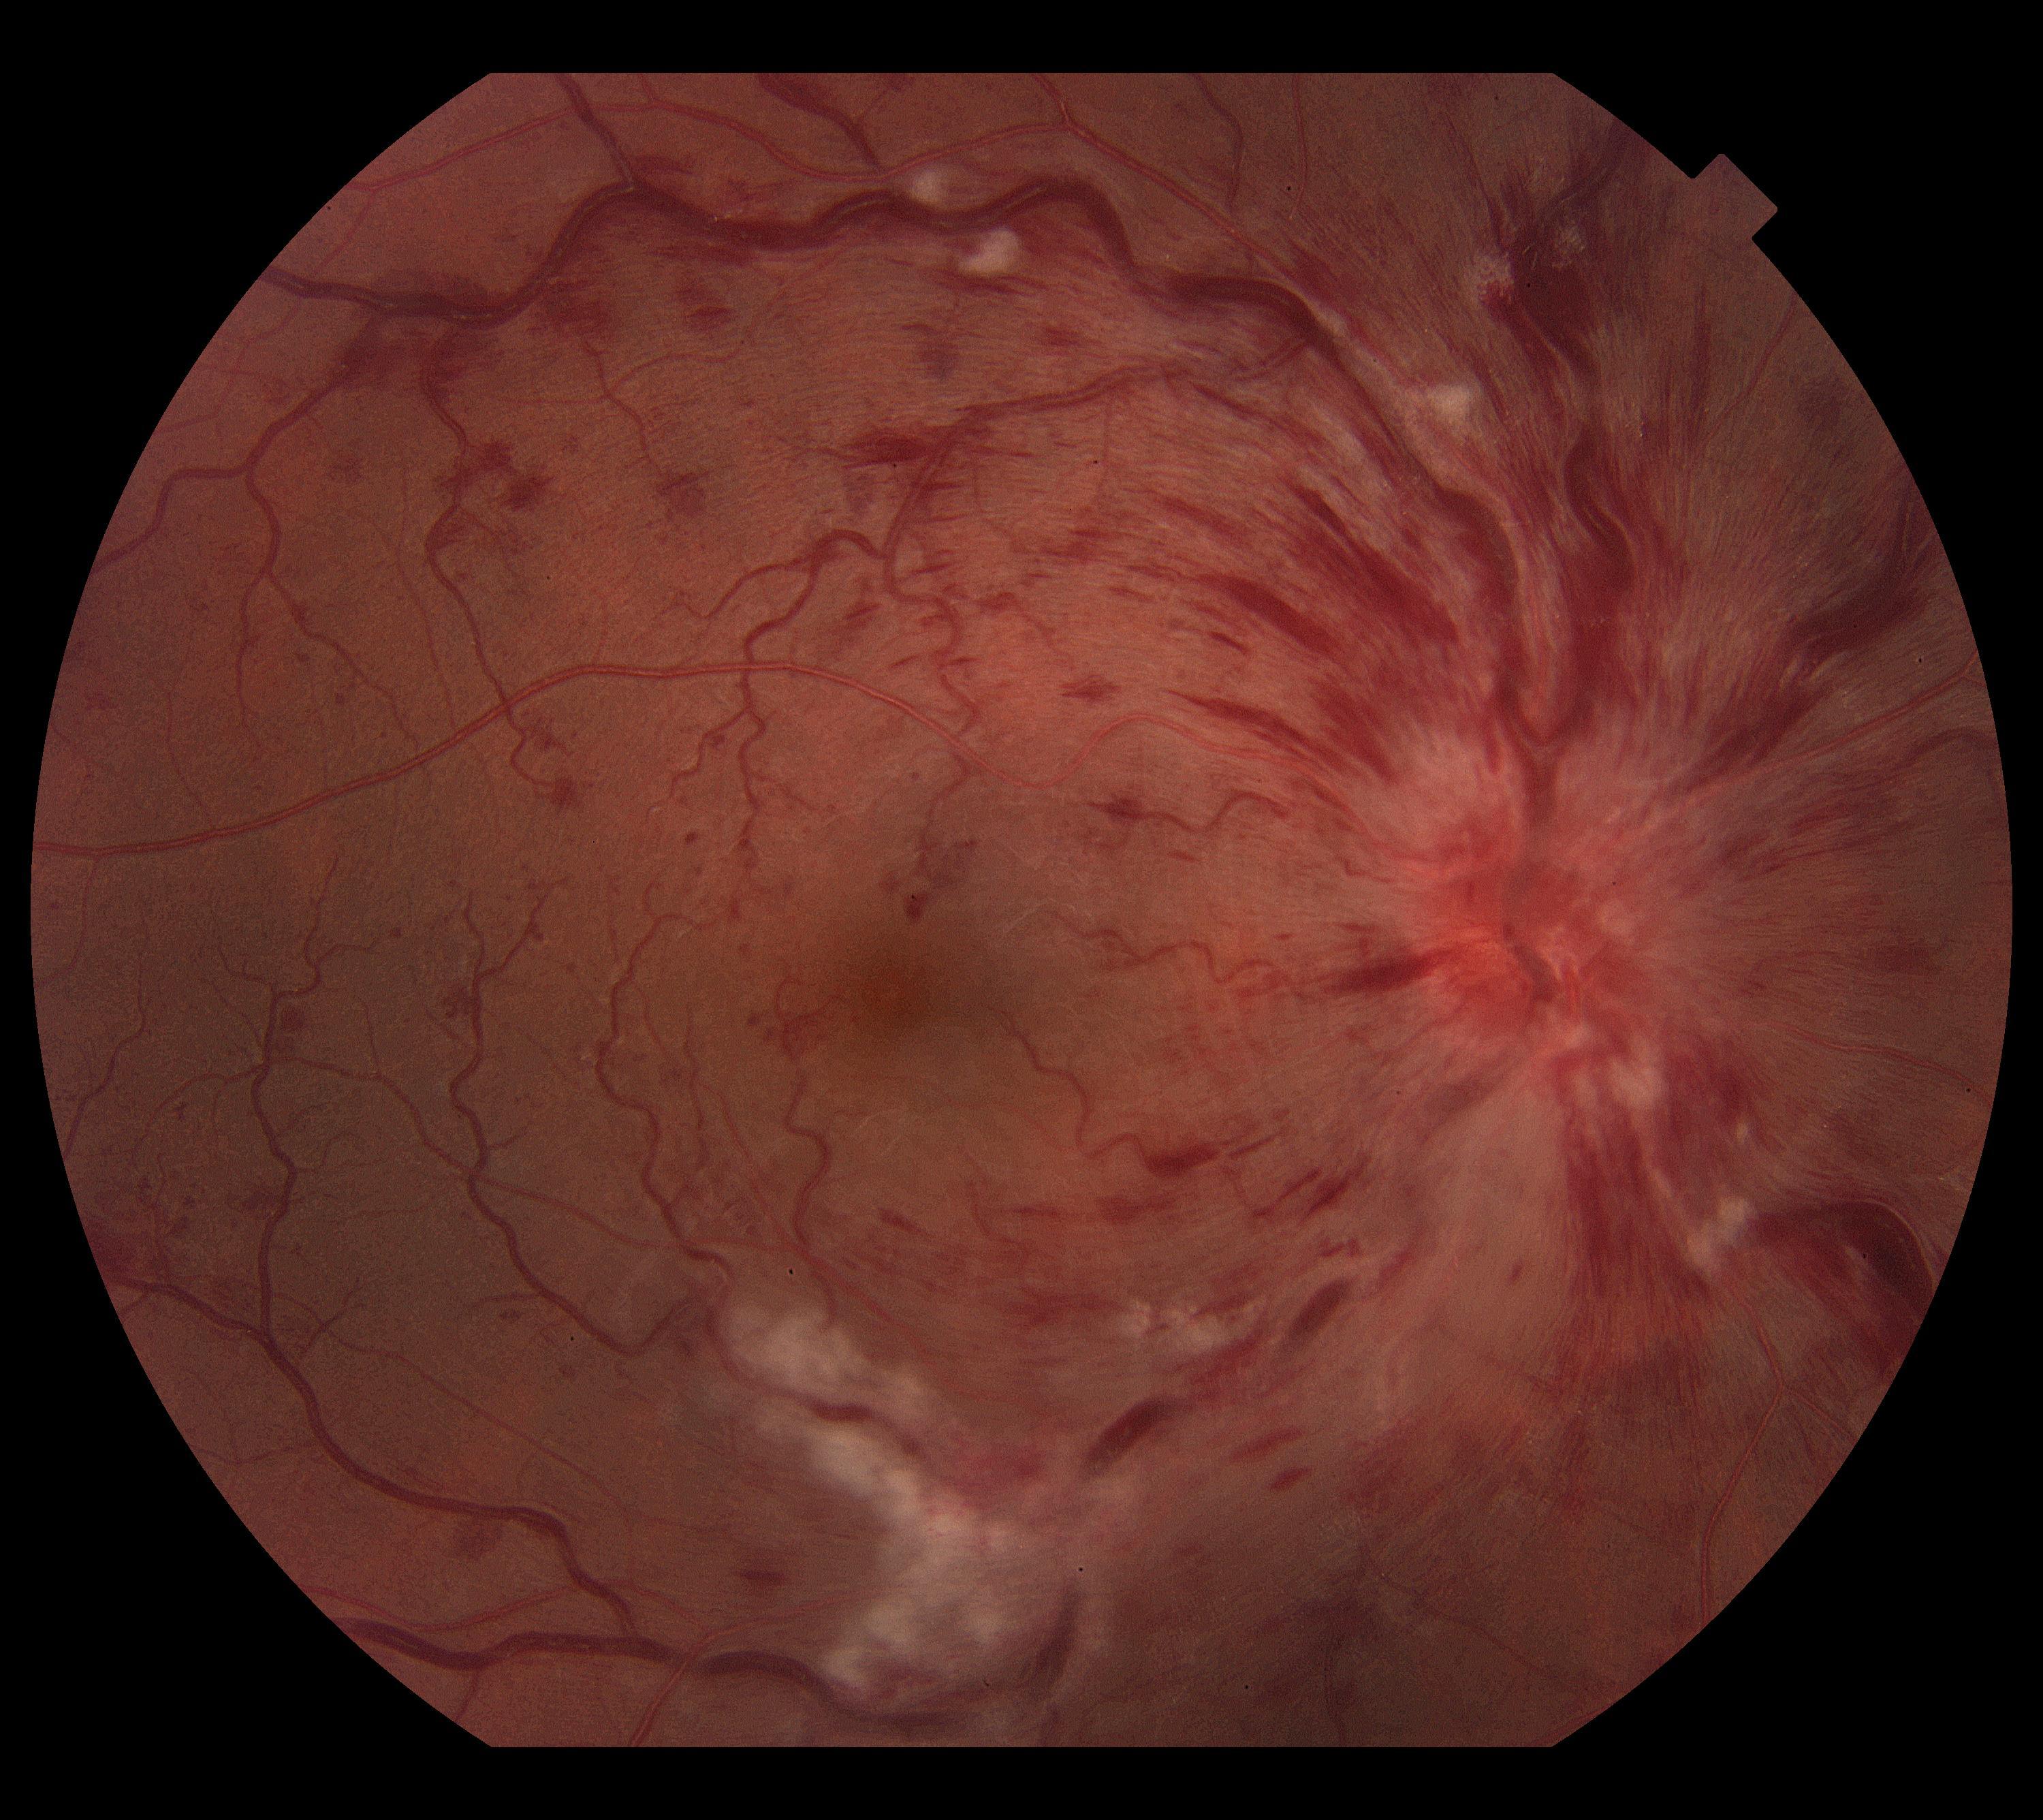

Retinal Vein Occlusion

Intravitreal injection for macular oedema following Retinal Vein Occlusions.